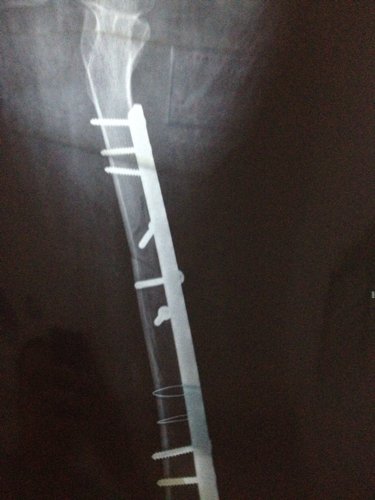

你好医生!左腿原来有小儿麻痹证,就在上个月11号不小心跌倒骨折13号做手术加钢板!现在在家休养。现在腰很痛?是怎么回事,有过性生活。现在简单吃两种药?请问医生像我这种情况会不会很难恢复原来那样?是不是还要吃些什么?还有要不要外敷些什么?还要腰很痛怎么办,谢谢!

病情分析: 图上所见,复位固定都还不错。 指导意见: 骨折的治疗重点是有效牢靠的固定。药物是次要的可以不服。也要注意尽量不要做对愈合不利的活动。除非是肌肉的锻炼等。